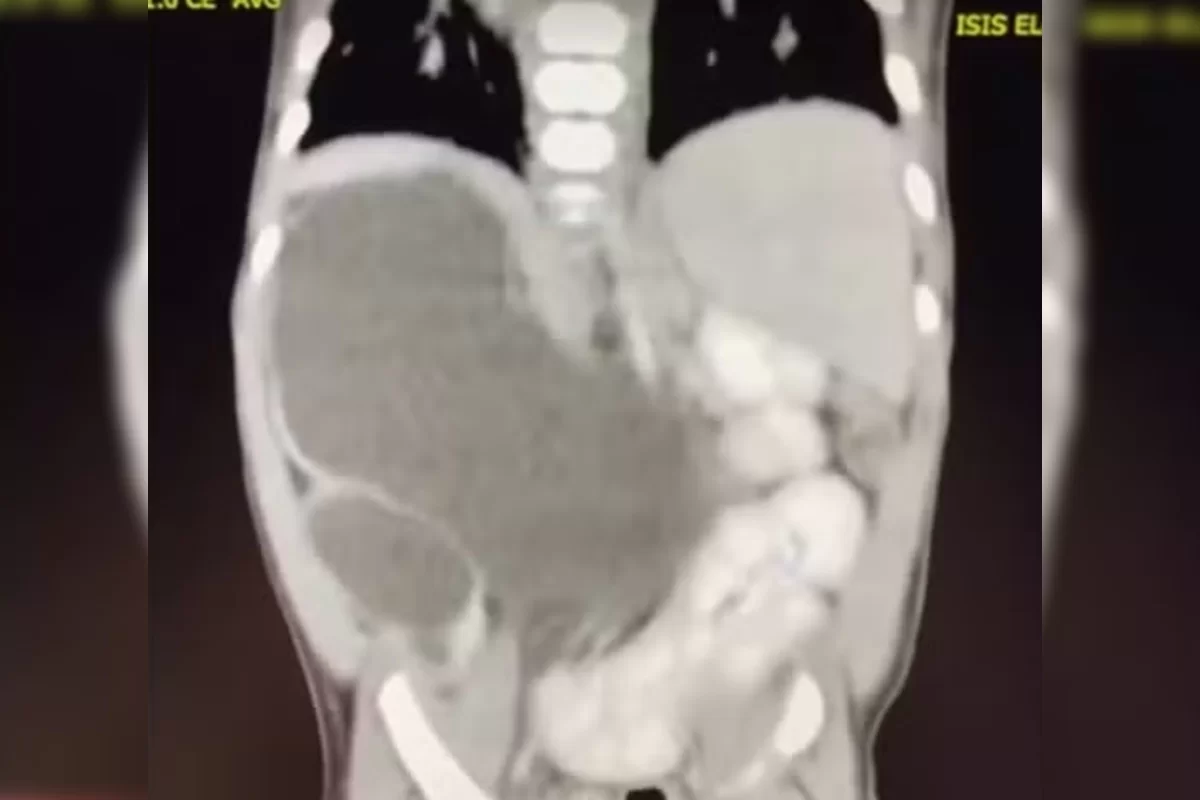

Isis Eloah Ferreira Alves, uma menina de 1 ano e 1 mês, é uma entre aproximadamente 100 casos no mundo de uma condição médica extraordinária: rins supranumerários, ou seja, quatro rins. A condição, uma má formação durante a gestação, demanda acompanhamento médico frequente.

Nascida prematura no Hospital de Sobradinho, em Brasília, Isis foi transferida para o Hospital da Criança José Alencar, onde a peculiaridade de seus órgãos foi descoberta. Aos 5 meses, ela passou por uma cirurgia para lidar com a condição. A mãe, Thalia Silva Alves, destaca que, apesar de alguns atrasos motores, Isis leva uma vida normal.